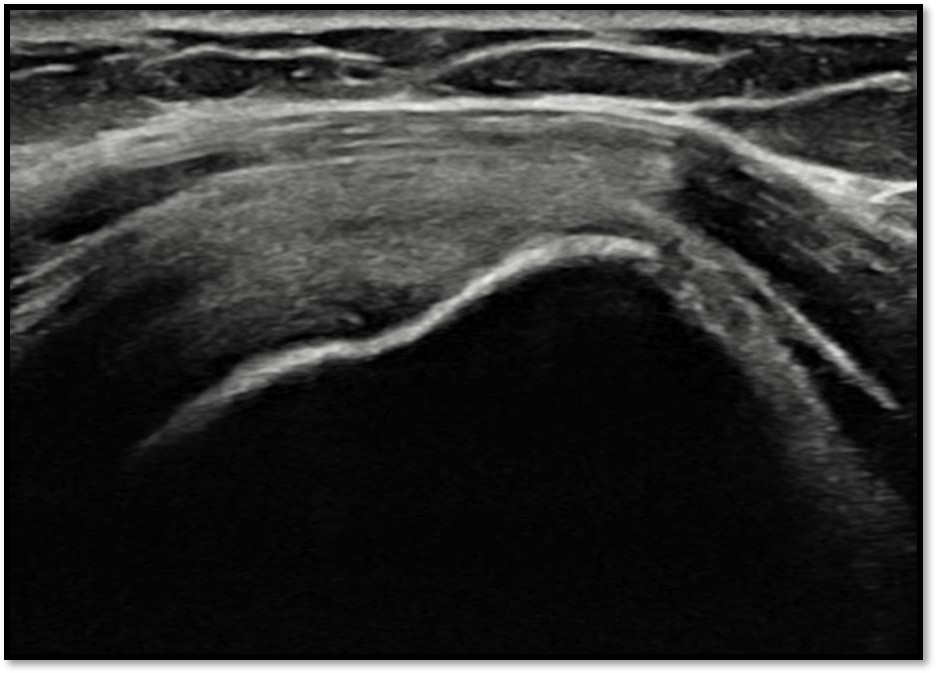

MRI를 검토해보았습니다. 확실히 회전근개 극상건에 부분파열이 있었습니다.

12주 후 초음파: 봉합 부위 안정적 유지

Q4. 제 파열이 어느 쪽인지 어떻게 알 수 있나요?

MRI 또는 초음파 검사로 확인할 수 있습니다. 단, 영상 판독은 전문성이 필요합니다. 플래티넘의원에서는 MRI를 직접 재검토하고, 초음파로 실시간 확인하여 정확한 위치와 양상을 진단합니다.